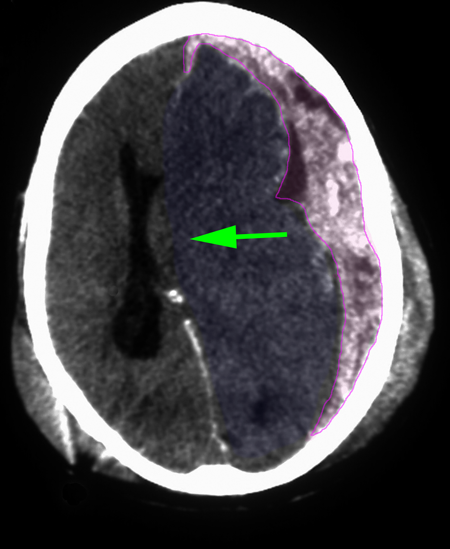

Subdural

Στα οξέα υποσκληρίδια αιματώματα οι αρχές της θεραπείας είναι ουσιαστικά οι ίδιες. Και εδώ απαιτείται άμεση παρέμβαση, γιατί η πρόγνωση χειροτερεύει σημαντικά μετά τις 4 ώρες από την δημιουργία του αιματώματος. Απαιτείται πολύ συχνότερα κρανιεκτομία, γιατί οι υποκείμενες βλάβες του εγκεφάλου είναι επίσης συχνότερες, και το οίδημα του εγκεφάλου μπορεί να αποτελέσει μείζον πρόβλημα διεγχειρητικά και μετεγχειρητικά. Το μέγεθός τους είναι συνήθως μεγάλο και κατά επέκταση η κρανιοτομία ή κρανιεκτομία που απαιτείται. Η μήνιγγα διανοίγεται πάντα και χρειάζεται και επίσης, μετά την αφαίρεση του αιματώματος, ανεύρεση και αιμόσταση του εγκεφαλικού αγγείου (φλέβα συνήθως) που αιμορραγεί. Τέλος εκτελείται μηνιγγοπλαστική και επανατοποθέτηση του οστικού κρημνού όταν εκτελείται κρανιοτομία, ενώ στις κρανιεκτομίες μπορεί να γίνει κρανιοπλαστική μετά από μερικούς μήνες.